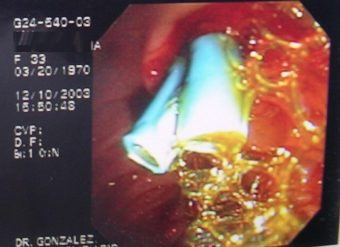

Colagiopancreatografía Retrógrada Endoscópica (ERCP)

Envíado por Gastroclínica